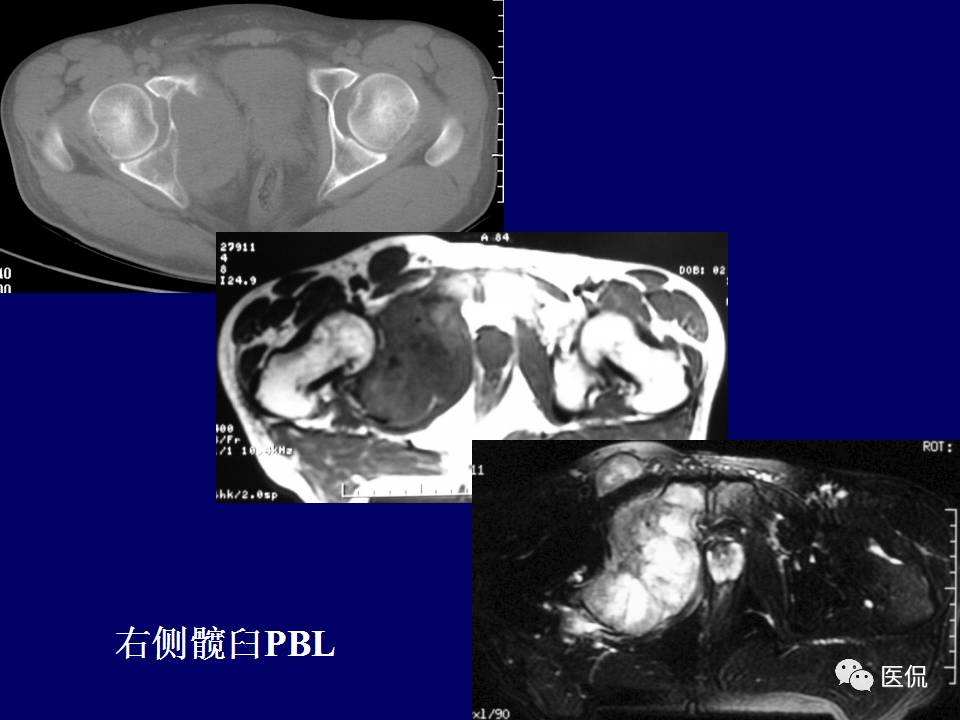

原发性骨淋巴瘤,是一种少见肿瘤。平片上干骺端单发、浸润性骨质破坏、层状骨膜反应+MR上骨髓侵犯、软组织肿块+年龄>30岁均可高度提示,影像学区分原发和继发PBL比较困难。更多知识,请往下看~